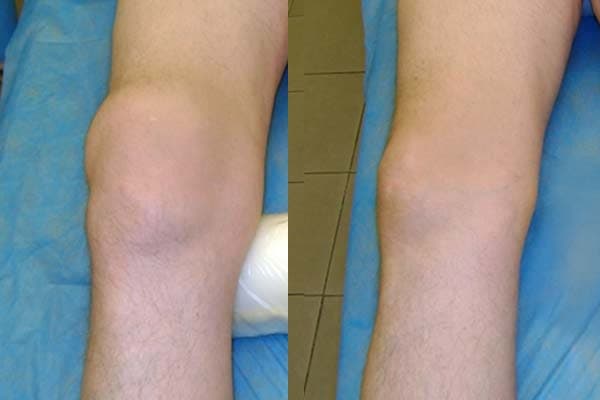

Inilah gambaran kerusakan sendi lutut pada hasil rontgen dan kenyataannya

Hasil pengobatan lutut.